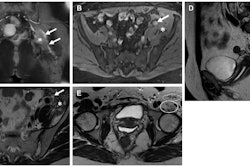

The dedicated ultrasound protocol was one for transvaginal ultrasound, which used a transducer of mid- to high frequency and allowed for higher spatial resolution. The dedicated MRI protocol for endometriosis included the following:

- T2-weighted turbo spin echo without fat-suppressed axial (including small field of view) and sagittal, with or without coronal views.

- T1-weighted gradient-echo in- and opposed-phase axial.

- Diffusion-weighted imaging and apparent diffusion coefficient mapping, axial.

- T1-weighted gradient-echo with fat suppression without IV contrast material, axial and sagittal, with or without coronal.

- T1-weighted gradient-echo with fat suppression, IV contrast, and subtraction.

- Axial and sagittal, with or without coronal.

- T2-weighted single shot fast spin echo, using a large field of view to include kidneys for evaluation of hydronephrosis.

The authors reported that, overall, routine ultrasound and MRI protocols had poorer performance than dedicated ones, which they suggested could lead to delays in diagnoses. They also found that ultrasound had better accuracy for identifying depth of wall invasion in bowel wall disease while MRI was better at visualizing pelvic wall and extraperitoneal disease.